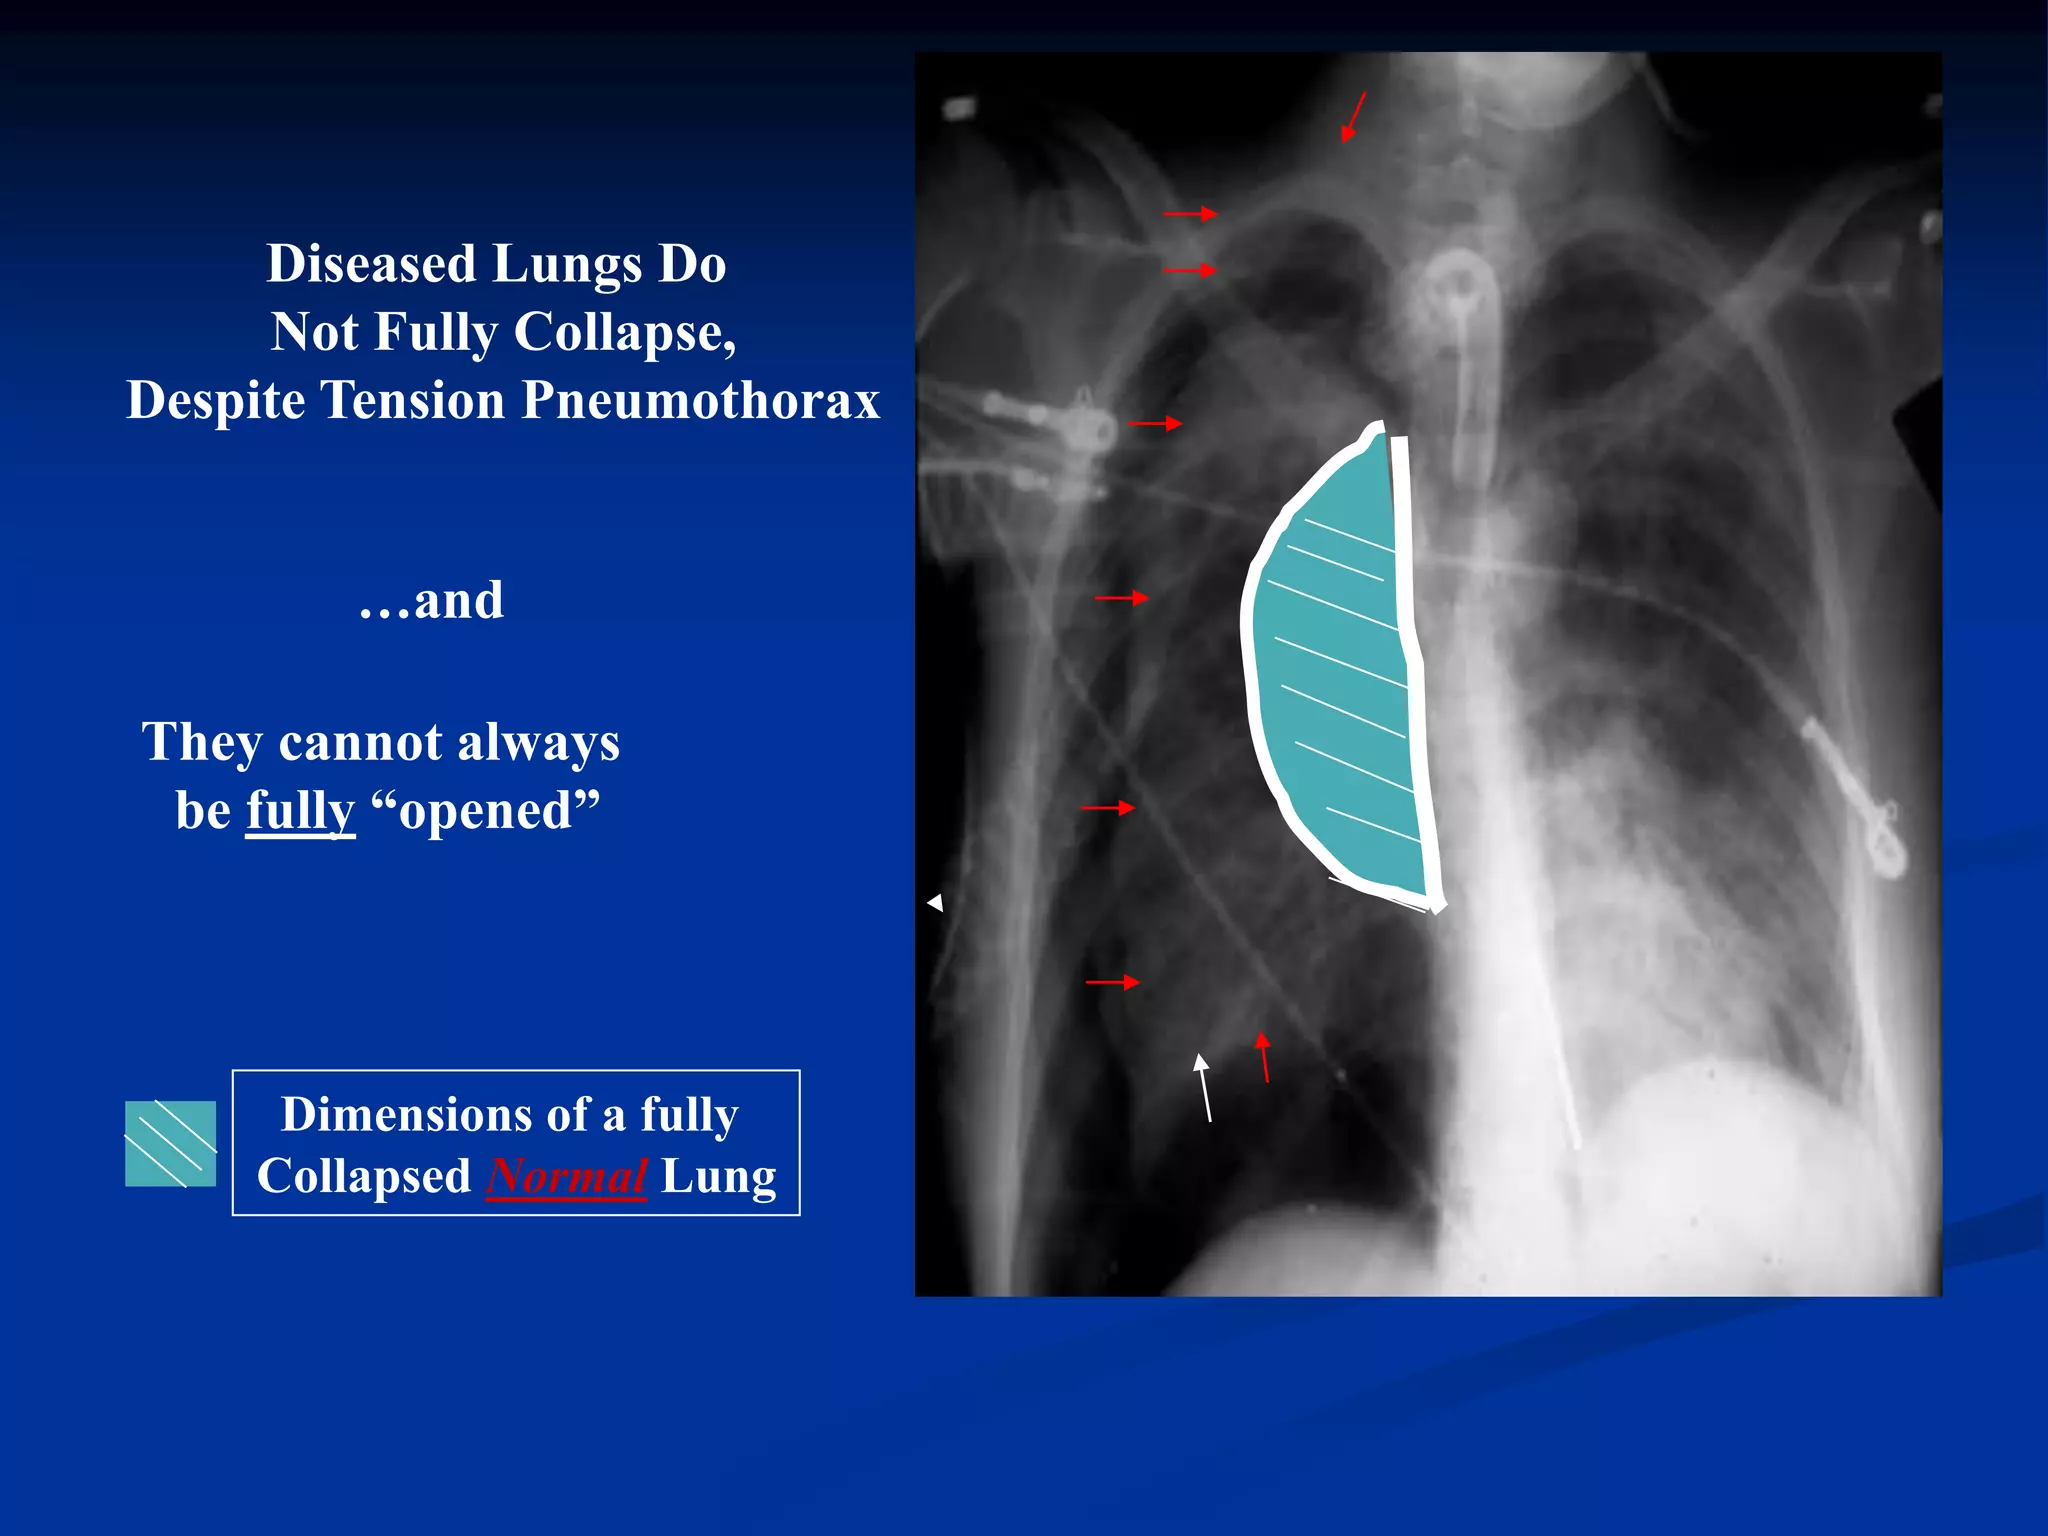

Diseased Lungs Do

Not Fully Collapse,

Despite Tension Pneumothorax

…and

They cannot always

be fully “opened”

Dimensions of a fully

Collapsed Normal Lung